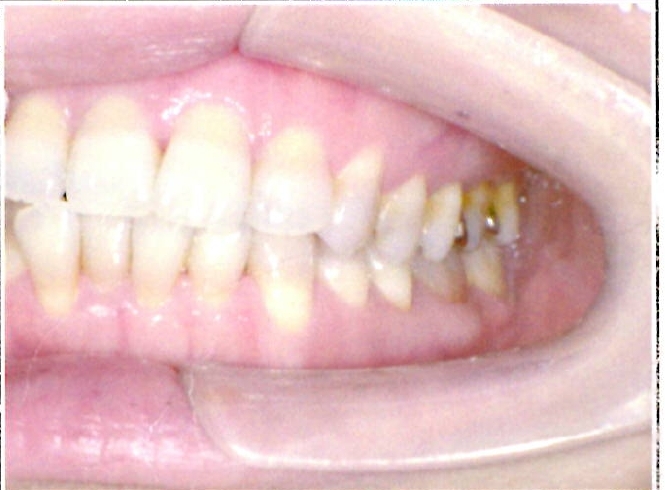

| 主訴・治療前の状態 | 過蓋咬合(噛み合わせが深く、下の前歯が見えない状態)により歯ぎしりができない状態でした。また、上下顎前歯部に叢生(クラウディング・ガタガタ)がありました。 |

| 治療内容 | 矯正治療により、過蓋咬合と上下の叢生を改善しました。 |

| 治療結果 | 適切な被蓋(上下の前歯の重なり)が得られ、下の前歯がきちんと見えるようになりました。上下の前歯の歯並びも美しく整い、しっかりと噛み合うようになりました。機能面・審美面ともに大きく改善した症例です。 |